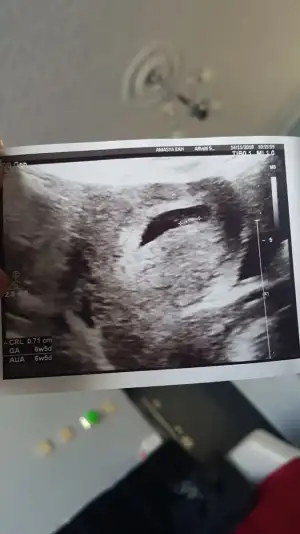

Kızlar bugün devletteki doktora gittim karından bakti aslında vajinadan bakalim dedi bende yok karından görülür dedim nitekim karindan göründü 6+5 cıktı 1 cm bile olmamış bebisim ama az kalmış resmide yükleyim size

• 20181114_103507.webp